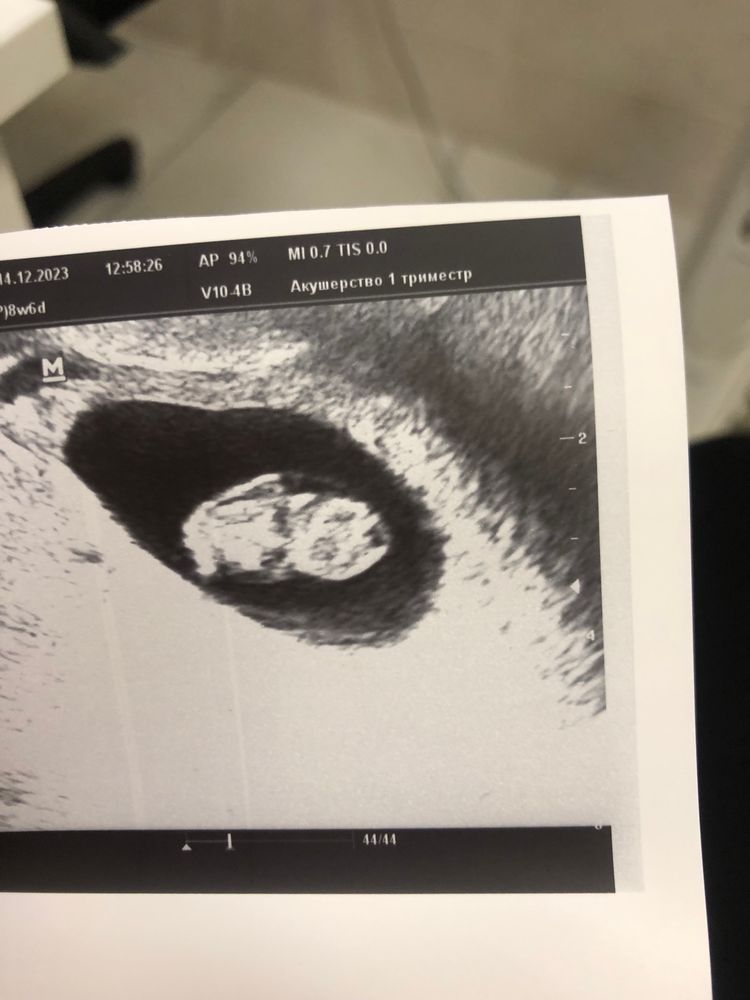

Посещение гинеколога, отслойка плодного яйца

Сегодня была у гинеколога , обнаружили причину кровянистых выделений , отслойка 19*5, около зева. Утром чуть бежево -розовое, позавчера вышел коричневый грязный цвет. Тонуса нет, малыш развивается , 8н6д КТР 2 мм, СБ 180 уд. Доктор оставил дома , постельный режим, терапия у меня домашняя :утрик, транексан, дюфастон, витамины и лежачее положение. Через неделю к нему на прием. Сказал не страшно около зева, все выходит и не пугаться😌